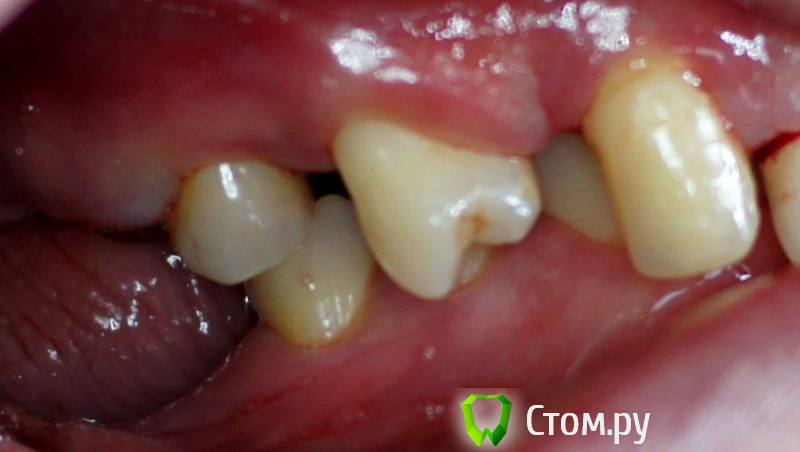

rin3225 Опубликовано 8 октября, 2014 Поделиться Опубликовано 8 октября, 2014 У пациента было желание сделать красивые зубы и улыбку!Проблема заключалась в массивной верхней челюсти , глубоком перекрытии и пациент не мог уйти без зубов! Отлив модели и выставив в центральную окклюзию было понятно, что без удаления всех зубов и поднятия прикуса с данной проблемой вопрос не решится. Обговорив все нюансы с пациентом,и получив согласие, было запланировано. заранее изготовлены акриловые протезы, предложено удаление всех зубов с одномоментной установкой имплантатов, внутриротавая сварка для первичной стабильности имплантатов и немедленная нагрузка 16 Ссылка на комментарий

Дмитрий Никитюк Опубликовано 8 октября, 2014 Поделиться Опубликовано 8 октября, 2014 У пациента было желание сделать красивые зубы и улыбку! Зачем так много имплантатов? Почему проволока приварена в поддесневом пространстве? Каким образом крепятся протезы? Ведь фиксация должна быть винтовая, а каркасс должен располагаться внутри протеза. 1 Ссылка на комментарий

Дмитрий Никитюк Опубликовано 8 октября, 2014 Поделиться Опубликовано 8 октября, 2014 Да понятно мне всё. Просто я категорически не согласен с подобным решением. Концепция применения сварки, которая мне импонирует, позволяет уменьшить количество имплантатов; надёжно их мобилизировать, обеспечив абсолютную неподвижность даже тех имплантатов, где торк был недостаточным; изготовить и зафиксировать протезную конструкцию в день имплантации; удешевить конструкцию; обеспечить пассивную посадку конструкции с винтовой фиксацией; облегчить последующее изготовление постоянной конструкции. В Вашем случае применение сварки считаю неоправданным. Вы так и не ответили на вопрос, зачем так много имплантатов? Второй вопрос, как Вы будете извлекать приваренную дугу перед постоянным протезированием. Ответьте на эти вопросы прежде всего себе, и Вы поймёте, что заблуждались... 3 Ссылка на комментарий